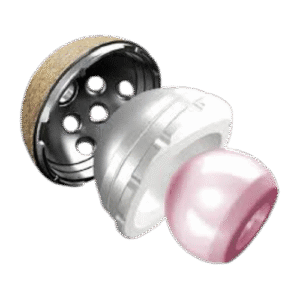

Reemplazo

articular

Artroplastia de rodilla y cadera para restaurar movilidad y aliviar dolor en articulaciones dañadas.